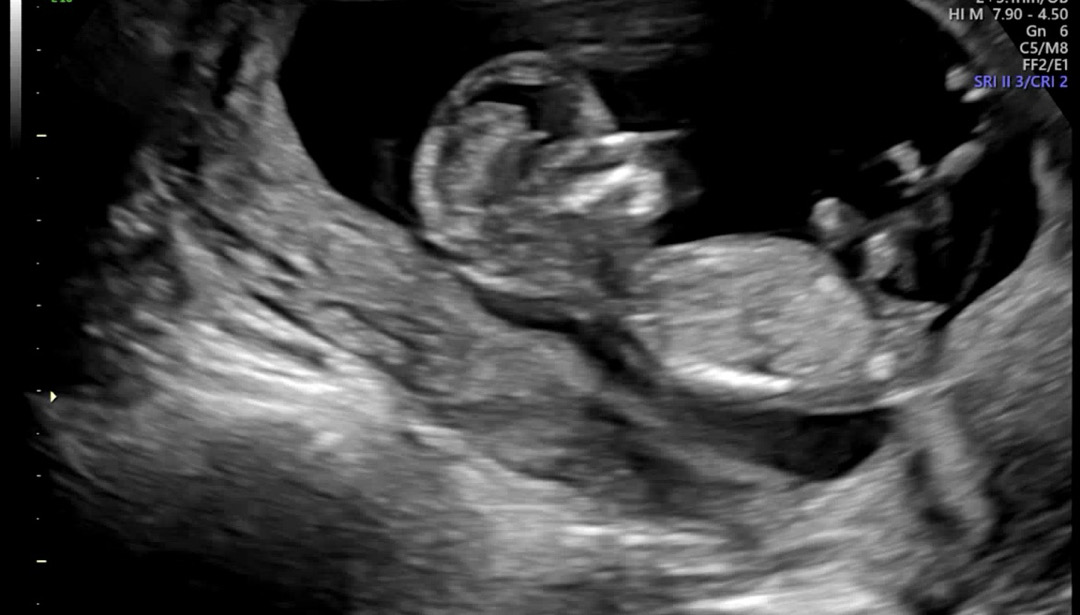

12주3일 각도법 봐주세요!!

저는 아무리 봐도 모르겠어요ㅠㅠ 각도법 잘보시는분들 도와주세요!

딸이네요

딸이네요^^